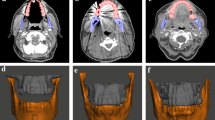

Delineation of the dental anatomy

Routine diagnostic computed tomography (CT) images were obtained from a patient undergoing treatment of a primary head and neck malignancy under a protocol approved by the Institutional Review Board at MD Anderson Cancer Center. Selection of the study patient was made based on the absence of significant dental artifact and the availability of diagnostic imaging with adequate sampling (≤1 mm slice thickness) through the region of the maxillary and mandibular dentition. The maxilla and mandible were individually contoured and segmented as separate structures using the Velocity oncology imaging informatics system (Varian Medical Systems, Palo Alto, CA) and exported to the stereolithography (STL) file format using the 3D Slicer open source medical imaging software platform (Fig. 1) [11].

The STL files containing the separate mandible and maxillary volumes were imported into 3D modeling software (Meshmixer, Autodesk Inc., San Rafael, CA). The mandible was treated as a rigid body and rotated and translated along the axis of the temporomandibular joint (TMJ) to simulate physiologic mandibular kinematics [12,13,14]. An incisal distance of 20 mm was used to approximate the desired jaw opening for radiotherapy treatment (Fig. 2).